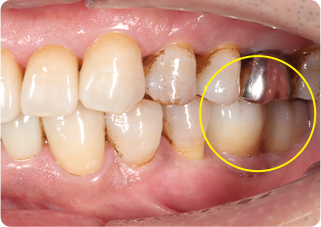

自家歯牙移植・精密根管治療・セラミッククラウン症例

術前

術後

| 主訴 | 奥歯の銀歯がぐらぐらして取れそう |

|---|---|

| 治療期間/回数 | 5ヵ月、10回 |

| 価格(税込) | 264,000円(税込) |

| リスク・副作用 | 生着不良、歯根吸収、骨性癒着の可能性 |

| ポイント | 銀歯の中でむし歯が進行し、保存不可能だったため抜歯し、後ろの親知らずを移植。移植の際に3Dプリンターで作製した親知らずのレプリカを使用し、治療時間の短縮と移植ポジションの確認を行った。生着するのを待ち、精密根管治療を行った後、セラミッククラウンを装着した。 |